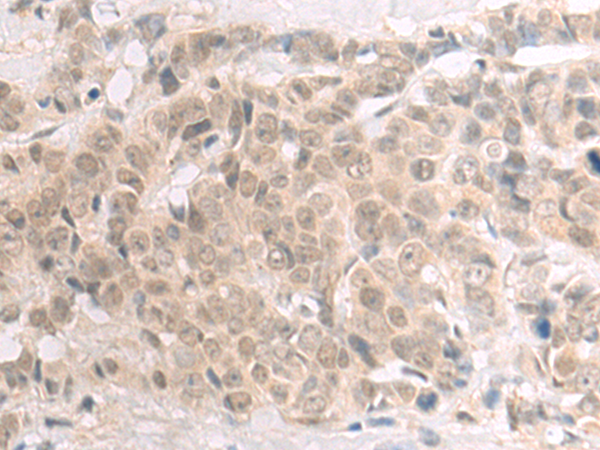

分类: 科研抗体货号: P09809别名: PLGP1应用: IHC反应种属: Human